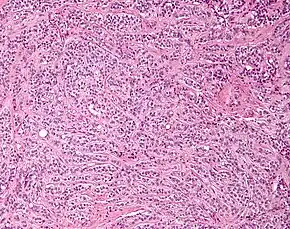

| Micrograph of a Sertoli cell tumour. H&E stain. | |

A Sertoli cell tumour, also Sertoli cell tumor (US spelling), is a sex cord–gonadal stromal tumour of Sertoli cells. They can occur in the testis or ovary. They are very rare and generally peak between the ages of 35 and 50. They are typically well-differentiated and may be misdiagnosed as seminomas as they often appear very similar.[1]